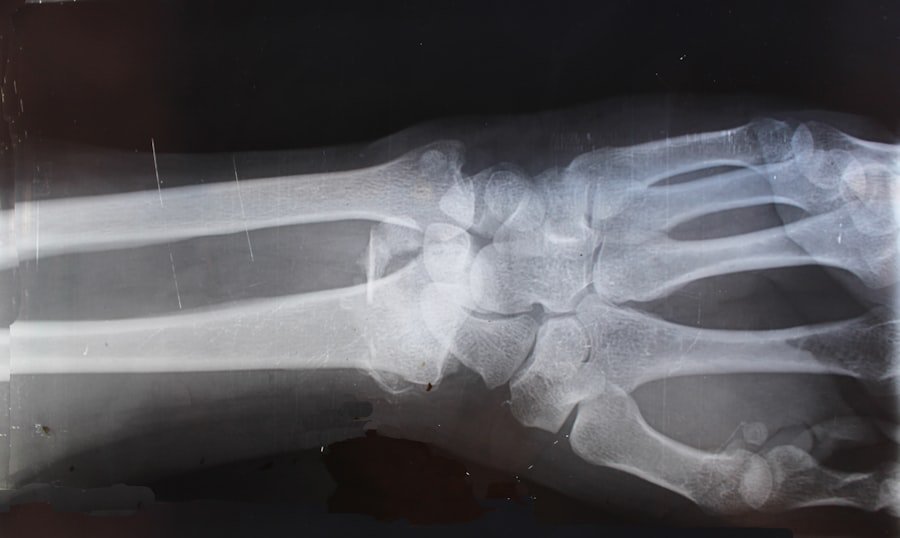

Workplace accidents can take many forms, each with its own set of causes and consequences. One of the most common types is slips, trips, and falls, which can occur due to wet floors, uneven surfaces, or cluttered walkways. These incidents can lead to serious injuries such as fractures, sprains, or head trauma.

For instance, a construction worker might slip on a wet surface while carrying heavy materials, resulting in not only physical injuries but also potential long-term disability. Another prevalent category of workplace accidents involves machinery-related incidents. Employees who operate heavy machinery or equipment are at risk of severe injuries if proper safety protocols are not followed.

For example, a factory worker might suffer a crushing injury if their hand gets caught in a machine due to inadequate safety guards or lack of training. Additionally, repetitive strain injuries are increasingly recognized as significant workplace hazards, particularly in office environments where employees may spend long hours typing or performing repetitive tasks without adequate breaks or ergonomic support.

| Common Types of Injuries | Most frequent injuries reported in workplace accidents | Sprains, fractures, cuts, burns, repetitive strain injuries | Injury type influences claim value and treatment duration |

After a workplace accident, seeking medical treatment should be a top priority for the injured employee. Not only does this ensure that they receive necessary care for their injuries, but it also creates an official medical record that can be used in support of their claim. Medical professionals will assess the extent of injuries and recommend appropriate treatment plans, which may include physical therapy, medication, or even surgery in severe cases.

Documenting injuries goes beyond just obtaining medical records; it involves keeping detailed notes about symptoms experienced over time and how these injuries affect daily life and work capabilities. For example, an employee who suffers from chronic pain after an accident may find it difficult to perform tasks they once managed easily. Keeping a journal that outlines daily challenges can provide compelling evidence of how the injury has impacted their quality of life and ability to work.

Injuries covered can range from physical injuries such as fractures, burns, and sprains to occupational illnesses caused by exposure to harmful substances or repetitive stress injuries. The key factor is that the injury must be work-related.